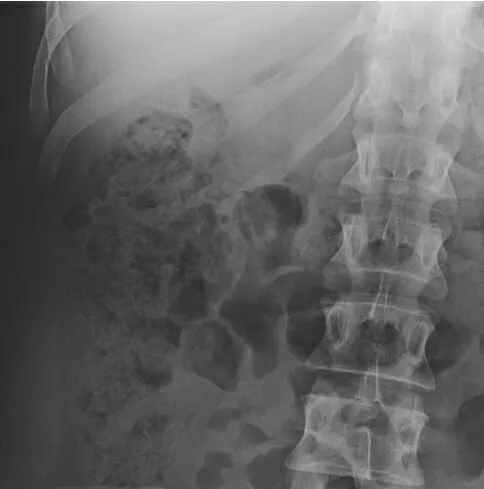

- Small Bowel Obstruction (SBO): Dilated small bowel loops >2.5 cm, central distribution, multiple air-fluid levels, valvulae conniventes visible. Common causes: adhesions, hernias.

- Large Bowel Obstruction (LBO): Dilated large bowel >6 cm (cecum >9 cm), peripheral distribution, haustra visible. Common causes: malignancy, volvulus.

- Bowel Obstruction: Dilated loops (SB >3 cm, LB >6 cm, cecum >9 cm), multiple air-fluid levels.